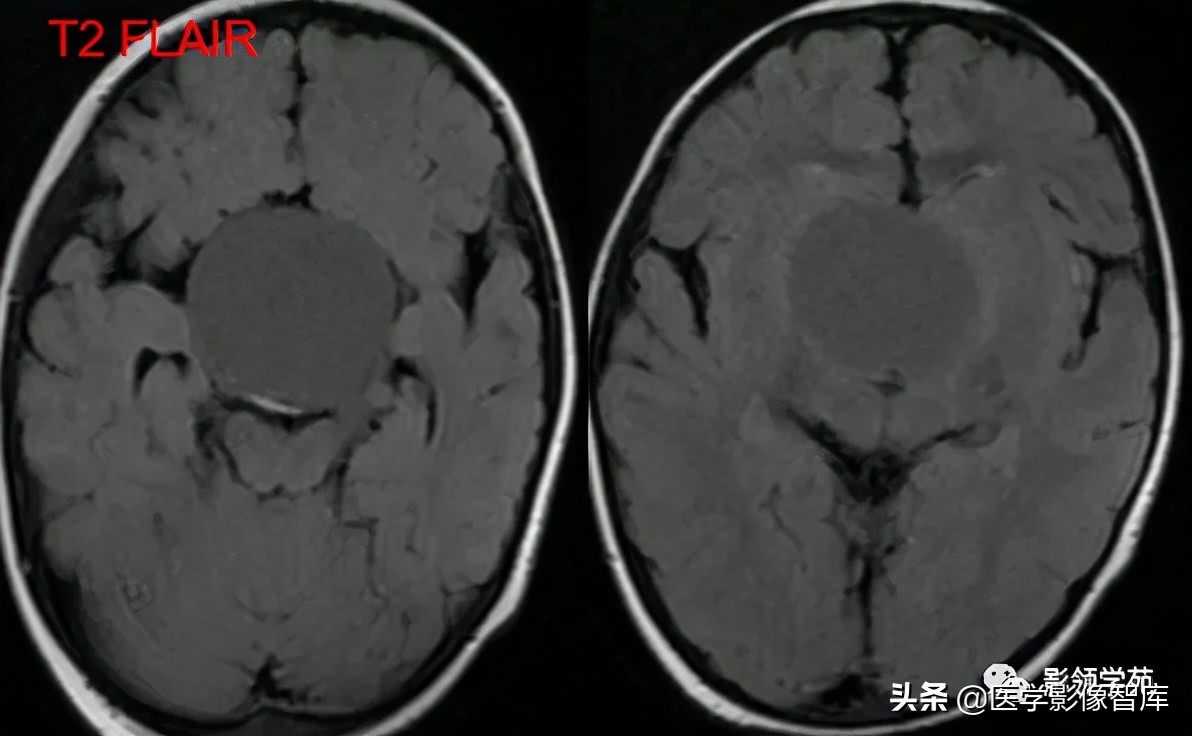

女 72岁,发现糖尿病3年余

鞍上区见一团块状稍高密度影,边界尚清,密度均匀。

鞍上右上方见一类椭圆形流空影。

病灶明显强化(瘤内血栓未强化),边界清楚,与右侧颈内动脉海绵段分界不清。垂体大小、形态未见异常。